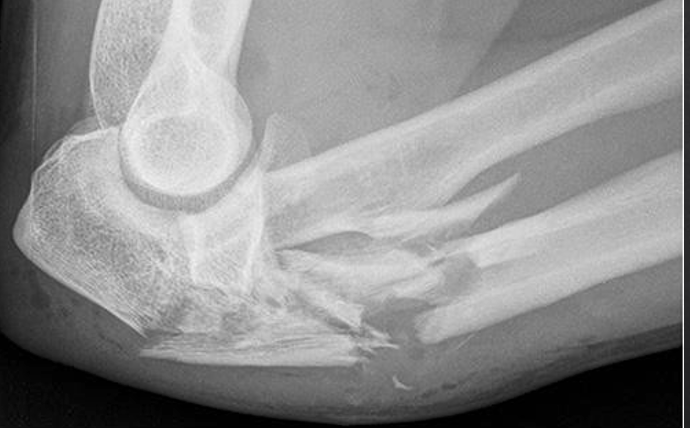

Q

in the shown radiograph

1- what type of fracture

2- site of fracture

3- describe anything else you can see

A

Left elbow. Open intra-articular comminuted fracture of the proximal radius and ulna, with air in the soft tissues